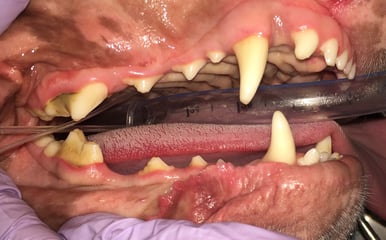

Below: Overview before procedure: (left and right)

%20-%20March%202024/Overview%20of%20right%20side%20before%20dental%20cleaning.jpg?width=386&height=240&name=Overview%20of%20right%20side%20before%20dental%20cleaning.jpg)

Below: Overview after procedure: (left and right)

. %20-%20March%202024/Overview%20of%20right%20side%20after%20dental%20cleaning.jpg?width=386&height=219&name=Overview%20of%20right%20side%20after%20dental%20cleaning.jpg)

Below: (left) Close up of non-vital 204 before RCT (right) Close up of non-vital 204 after RCT

*Note that performing root canal therapy cannot remove all of the staining located in the dentinal tubules.

Tucker is thriving at home! At 7 years old, he hasn't slowed down one bit. Being a beloved pet of the ADRS staff, we get to see him frequently. Although his tooth will always remain discolored, he is pain-free and undergoes annual anesthetic dental procedures to ensure there are no issues with his previous root canal therapy.